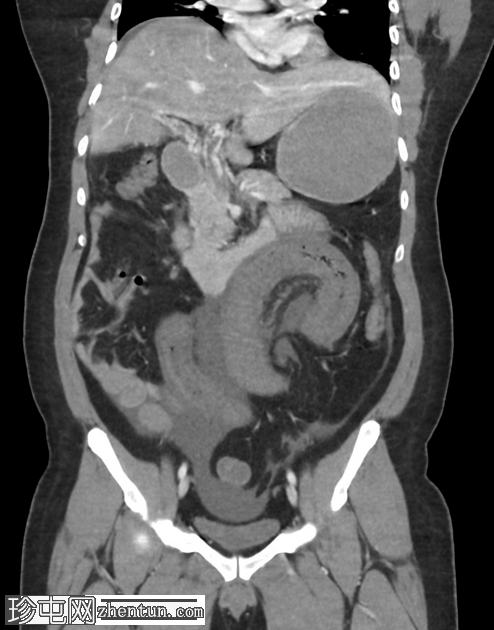

冠状C+门静脉期

肠系膜上静脉及其主要支流广泛血栓形成,延伸至脾静脉和门静脉,包括门静脉右支和近端左支。

小肠管增厚、水肿、低灌注,提示小肠缺血。

由于门静脉右支血栓形成,肝右叶低灌注,导致短暂性肝密度差(THAD)。

胃部膨胀,充满液体。

腹部少量游离液体。